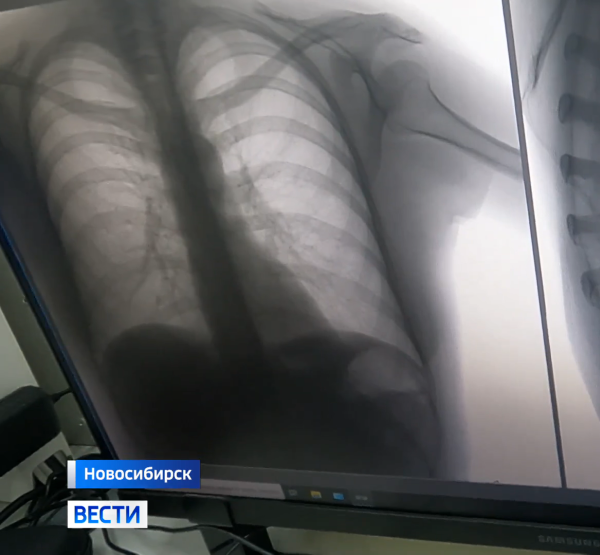

Одна из самых распространённых инфекций в мире. Носитель — каждый третий к сорока инфицирован практически каждый. Туберкулёз. От него не спрятаться: социальный статус последнее, что «интересует» палочку Коха. Именно поэтому флюорография — самый доступный способ диагностики — показана всем взрослым.

Мобильный флюорограф у главного ж/д вокзала Новосибирска. Высокая проходимость то, что нужно организаторам. Чем больше людей заметит машину и волонтёров, тем больше обратят внимание на собственное здоровье.

Очередь меньше, чем порой в поликлинике. Паспорт, пять минут — всё. Через несколько дней результат будет в участковой поликлинике. Перезвонят только если что-то вызовет беспокойство. Без преувеличения — спасительная акция.